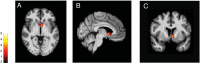

Although pain is a widely known phenomenon and an important clinical symptom that occurs in numerous diseases, its mechanisms are still barely understood. Owing to the scarce information concerning its pathophysiology, particularly what is involved in the transition from an acute state to a chronic condition, pain treatment is frequently unsatisfactory, therefore contributing to the amplification of the chronic pain burden. In fact, pain is an extremely complex experience that demands the recruitment of an intricate set of central nervous system components. This includes cortical and subcortical areas involved in interpretation of the general characteristics of noxious stimuli. It also comprises neural circuits that process the motivational-affective dimension of pain. Hence, the reward circuitry represents a vital element for pain experience and modulation. This review article focuses on the interpretation of the extensive data available connecting the major components of the reward circuitry to pain suffering, including the nucleus accumbens, ventral tegmental area, and the medial prefrontal cortex; with especial attention dedicated to the evaluation of neuroplastic changes affecting these structures found in chronic pain syndromes, such as migraine, trigeminal neuropathic pain, chronic back pain, and fibromyalgia.